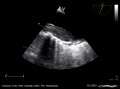

Transesophageal ultrasound

The transesophageal echocardiogram (TEE) is a relatively good test in the diagnosis of aortic dissection, with a sensitivity up to 98% and a specificity up to 97%. It has become the preferred imaging modality for suspected aortic dissection. It is a relatively noninvasive test, requiring the individual to swallow the echocardiography probe. It is especially good in the evaluation of AI in the setting of ascending aortic dissection, and to determine whether the ostia (origins) of the coronary arteries are involved. While many institutions give sedation during transesophageal echocardiography for added patient comfort, it can be performed in cooperative individuals without the use of sedation. Disadvantages of TEE include the inability to visualize the distal ascending aorta (the beginning of the aortic arch), and the descending abdominal aorta that lies below the stomach. A TEE may be technically difficult to perform in individuals with esophageal strictures or varices.

-

Aortic dissection with a intramural hematoma as seen on TEE